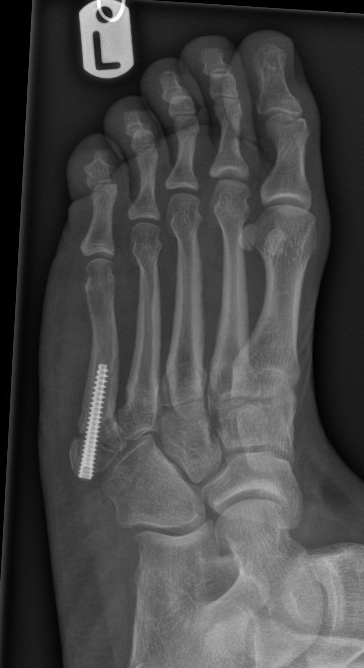

Figure 3: 3 months post fixation